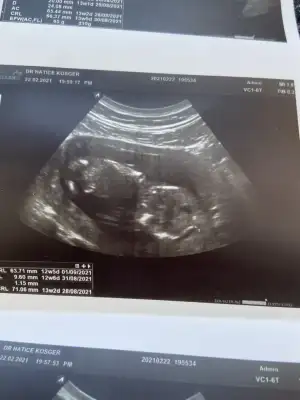

Kızlar herkese selam:) Bugün benim de kontrolüm vardı normalde 11. Haftadayız 12+3 çıktı, gidene kadar doğru dürüst bir şey hissetmiyordum yani bulantılar, ikinci çocuk nasıl olacak endişeleri fln sarmıştı.. ama bugün ultrasonda öyle net gördük ki kıpır kıpır hareketliydi parmaklarına kadar görebildik:) cinsiyeti göremedim dedi ya da görüp söylemedi bilmiyorum, ikili için ölçüm yapıldı üzerine hastaneye gidip kan verdim orada da muayene oldum kan verebilmek için erkeğe benzettim ben dedi... bir oğlum var gönül ister ki ikinci kız olsun ama yeter ki sağlıklı olsunlar zaten öğrenene kadar sürüyor bu heyecan öğrendikten sonra hepsi bir :) Bizden haberler böyle dilerim güzel haberler aldığımız bir hafta olur hepimizin